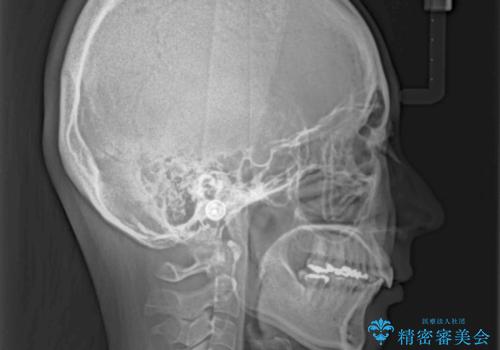

- 上下の出っ歯を気にして来院された患者様です。

口元を積極的に引っ込めるために、上下左右の第一小臼歯を4本抜歯することとしました。

元々ディープバイトのため、スペースを閉じている期間に上下前歯が接触してしまい、治療期間が想定よりも伸びてしまいました。